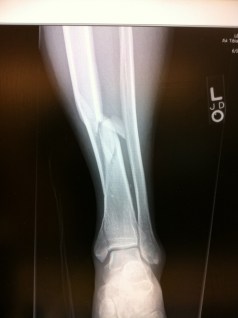

I broke my leg a couple of years ago, a wicked Tib/Fib + ankle break.

Meanwhile back at Gresham medical center I still have not seen my x-rays. Fortunately a nurse understood my concerns and snapped a couple of pictures of the computer screen on her iPhone and sent them to me. The shot at the top of this blog is one of those pictures. I take one look and know I am in trouble, this is no normal surgery if I want leg length and rotation to stay normal. I take the images and email them to Dr. David Paul Barei and call him, Yens Chapman introduced me to Dr. Barei. Because Dr. Barei knows me and knows I would not call if it was not urgent he steps out of rounds to take my call. One look at the x-rays and he says:

– well these are going to be complicated. Did they talk to you about the fracture in the ankle joint? No, well that is going to be tough and did they talk with you about the vascular damage? No, well it looks like you leg rotated more than 180 degrees when it was broken and I would estimate you have a 50% chance of keeping your lower leg. You need to get yourself transferred to Harborview now. I explain they refuse to transfer me and he says: “What do you mean they will not transfer you? Put the Dr on please. I hand my phone to the local Dr basically says a few yes’s and a few no’s in response to Dr. Barei’s questions and then says OK, hands me back the phone and says I am getting transferred to Harborview.